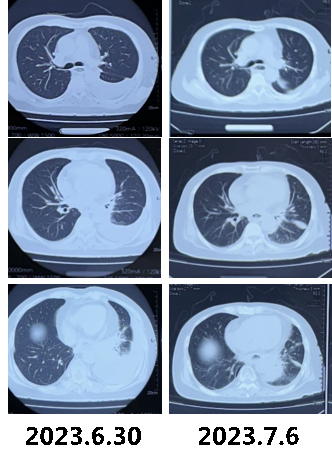

半月余前(2023.6.30)因胸痛、咳嗽无缓解,于外院行胸部CT示左肺下叶团片状高密度影,左侧胸腔积液,2023.7.3外院住院治疗。行左侧胸腔闭式引流术(7.4-7.10),共引流1000mL黄色浑浊胸水,胸水化验:白细胞3500/mm3,多核88%,ADA 10.5U/L,总蛋白55.2g/L,LDH 145U/L,培养见白色假丝酵母菌,病理未见肿瘤细胞。2023.7.4起患者出现发热,Tmax 38.6℃,热型无规律,给予“哌拉西林他唑巴坦 5g q12h(7.3-7.4)”“舒普深2g q8h(7.5-7.6)”,体温无好转,复查胸部CT(2023.7.6)示左肺下叶团片影较前进展。

患者进食红心火龙果约1小时后,胸水呈粉色;患者于本院胸水培养见白念珠菌,而白念珠菌难以由肺内播散至胸膜;外院胸水及BALF培养见白色假丝酵母菌,BALF-NGS提示白色念珠菌,且患者既往有食管手术史,不能排除食管-胸膜瘘可能,我们追踪了患者2022年的胸部CT。可以看出,患者2022年胸部CT纵隔窗见明显食管-空肠吻合口缝合痕迹,而自2022.6.30起,吻合口处缝合脱落。